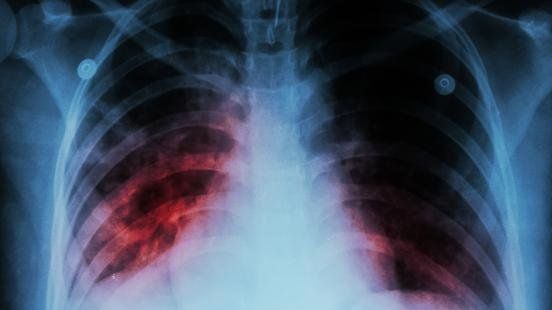

Un informe publicado por el Centro Europeo para la Prevención y el Control de Enfermedades (ECDC) y la Organización Mundial de la Salud (OMS) reveló que el covid-19 desplazó a la tuberculosis como la enfermedad infecciosa con mayor índice de mortalidad.

En el informe titulado "Vigilancia y seguimiento de la tuberculosis en Europa 2021" y reseñado por Gaceta médica también se advierte que la pandemia podría poner en peligro los avances que se han hecho con respecto a la tuberculosis.